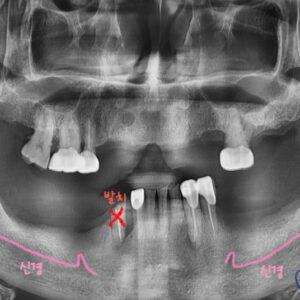

위 아래 치아 대부분이 부러져서 치아 뿌리만 남고,

남은 치아들은 충치가 심해서 저작기능을 할 수 없는 상황이셨는데요.

엑스레이 상에도 남은 치아의 상태가 안 좋은게 보입니다

위에 치아들은 상태가 많이 안 좋아서 전부 발치 할 수 밖에 없었지만,

아래 치아라도 최대한 살려 치료 해보기로 했습니다

아래 치아는 신경치료 후 크라운, 보험 임플란트 2개를 활용해 보험 부분 틀니로 진행했습니다.